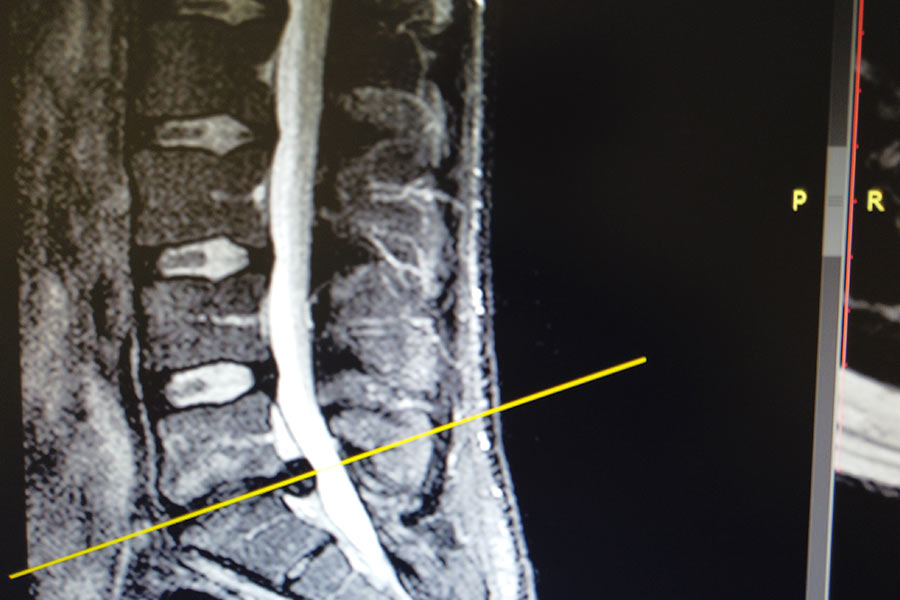

Hernia L5S1 dolor ciática

La pequeña hernia encontrada el pasado año ha empeorado y está presionando el nervio y es necesario extraerla antes de que los síntomas empeoren.

resonancia-hernia-l5s1-ciática-icac-2